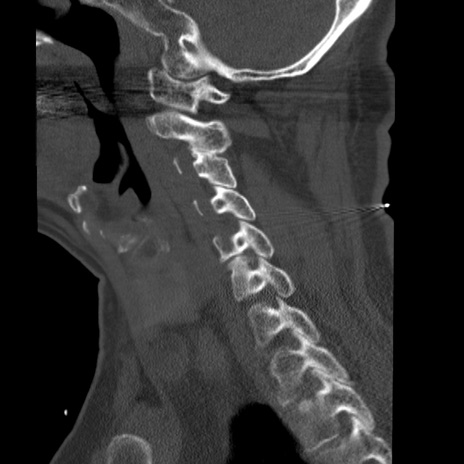

症例50 頚椎CT(矢状断像)

【症例】60歳代女性

【主訴】後頭部〜右後頸部にかけての痛み

【現病歴】本日飲食店でコーヒーを飲んでいたところ、突然後頭部〜右後頸部にかけて痛みが出現し、右上肢の感覚障害を伴ったため救急要請。

【身体所見】脳神経学的に明らかな異常所見を認めず。右上肢に軽度の感覚障害あり。

異常所見と診断は?

頚椎CT